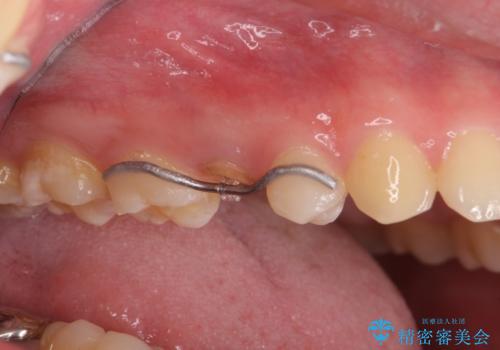

右上の被せものを除去したところ、中で歯が割れていたため、部分矯正で引っ張り出すことになりました。

・両どなりの歯に一時的にワイヤーを接着します。